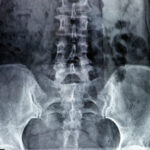

Sepsis is a life-threatening condition that arises when the body’s response to an infection damages its own tissues and organs. It can progress rapidly to septic shock, multiple organ failure and death if not recognised and treated urgently. When healthcare professionals fail to identify or manage sepsis properly, this may amount to medical negligence with potentially fatal consequences.

The classic red-flag symptoms of sepsis include high or low temperature, fast heart rate, fast breathing, confusion, extreme pain or discomfort, clammy or mottled skin, and reduced urine output. When these signs are missed, misdiagnosed as flu, gastroenteritis or a minor infection, or when treatment is delayed, medical negligence often leads to severe disability, limb amputation or death that could have been prevented.